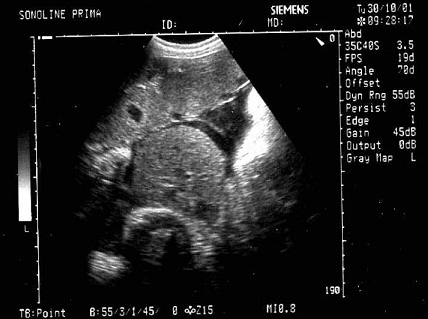

女性,26岁,停经29周,产前B超检查如图,超声诊断为()。

A:胎盘早期剥离

B:正常中期妊娠

C:胎儿脐带绕颈

D:胎儿畸形,腹壁裂

E:畸胎瘤